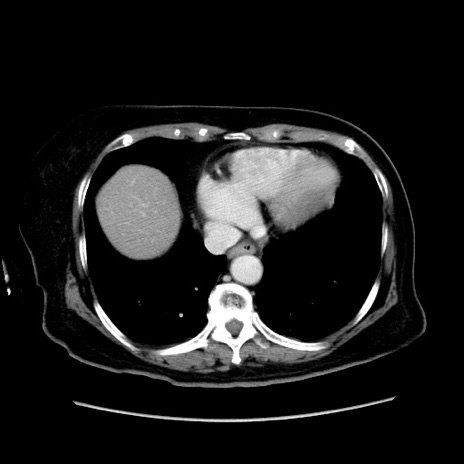

症例19(横断像)

【症例】80歳代女性

【主訴】下腹部痛

【現病歴】約8時間前より下腹部痛の出現あり、救急外来受診。

【既往歴】両側付属器切除

【身体所見】意識清明、下腹部正中に手術痕あり、その部位に一致して圧痛と反跳痛あり。腸蠕動音は亢進。

【データ】WBC 9300、CRP 0.15